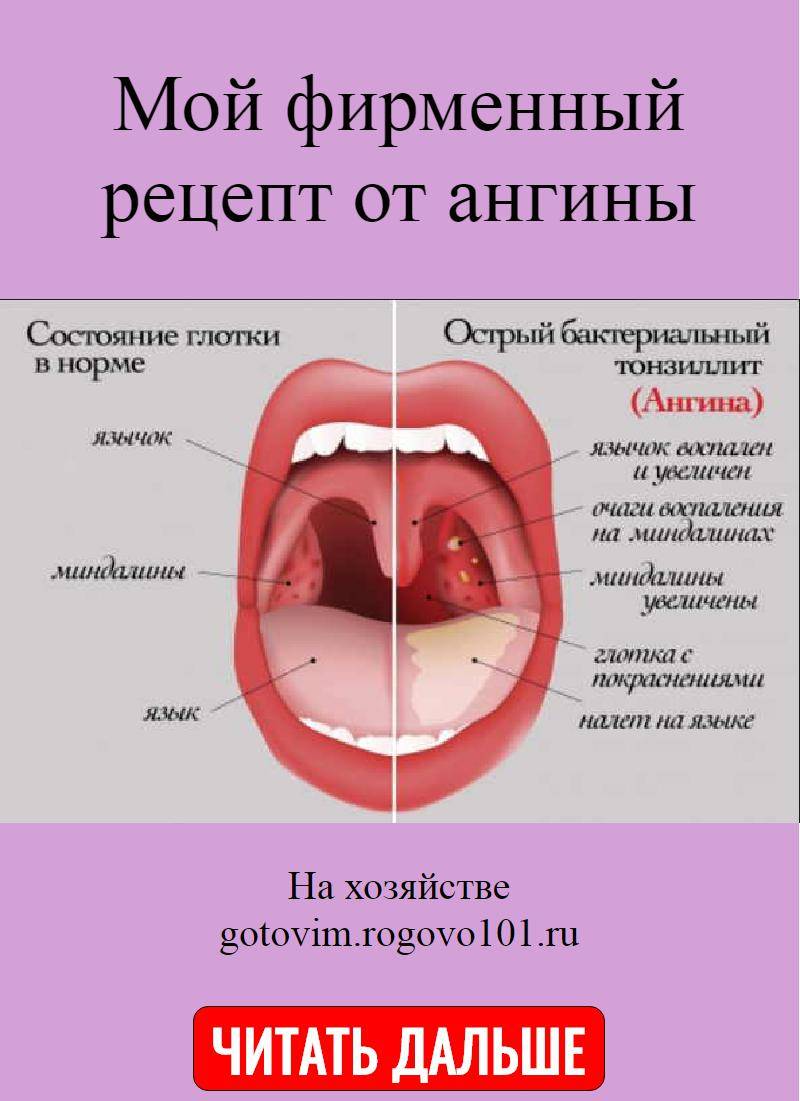

Небные миндалины (или гланды) играют особую роль в системе местного иммунитета, поскольку первыми принимают на себя атаки патогенных микроорганизмов, которые попадают в ротовую полость ребенка. При поражении вирусами, бактериями гланды принимают активное участие в выработке особых антител, действие которых направлено на уничтожение болезнетворной микрофлоры. Такая реакция приводит к появлению воспалительных процессов, увеличению небных миндалин и возникновению гнойных очагов.¹

Независимо от формы заболевания, у ребенка проявляются такие симптомы:

- повышение температуры тела до 38-39°С и выше;

- сильная боль в области горла, которая беспокоит даже при вдыхании воздуха или разговоре;

- слабость, вялое состояние и недомогание;

- резкая боль при глотании слюны, пищи;

- увеличение лимфатических узлов, расположенных в области шеи.

Если ангина проявилась у грудничка, то он может часто капризничать, отказываться лежать самостоятельно. Дополнительно могут наблюдаться воспаление слизистых оболочек глаз, кашель, раны в ротовой полости. В редких случаях возникает осиплость голоса, неприятный вкус во рту. В детском возрасте признаки заболевания выражены более остро, нежели у взрослых пациентов. Продолжительность болезни зависит от ее типа, возраста больного. При правильно подобранном и вовремя назначенном лечении удается вылечиться в течение 6-8 дней.